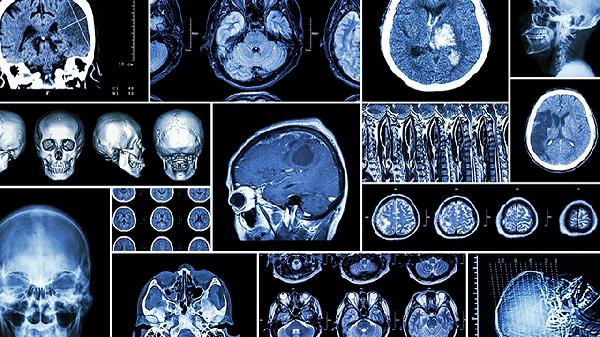

脑血栓患者日常需保持低盐低脂饮食,每日钠盐摄入不超过5克,增加深海鱼类和坚果摄入以补充不饱和脂肪酸。适度进行肢体康复训练,从被动关节活动逐步过渡到主动运动。控制血压血糖在目标范围,戒烟限酒,保证充足睡眠。定期复查头颅CT或核磁共振,监测病情变化。出现头痛加剧、意识模糊等异常情况应立即就医。